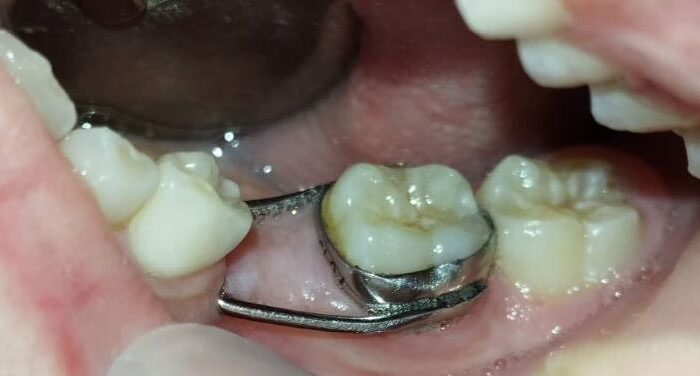

حافظات المسافة السنية – متى يكون تركيبها ضرورياً وما أشكالها؟